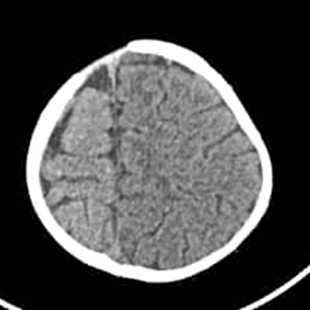

We report in this paper the picture of a child K, male, 1-year-old, weighing 9 kg, received at the neuropsychiatric center. Born at term, normal delivery with a birth weight of 4,100 kg. One day later, he was put in an incubator without oxygenation. He is the 7th in a family of 7 children with a history of malformation reported in the family or epileptic seizures. Her mother reports regression in milestone (speech and walking). On examination, we find cranial dysmorphism made up of an asymmetrical head with the right hemiface more prominent than the left (Figure 1), right hemicorporal erythroderma from head to foot taking the inner and posterior face (Figure 1) and describing an atypia by taking half of the sole of the right foot (Figure 2) while the left hemibody is of normal colour. There are left hemicorporal tonic-clonic convulsive seizures which become generalized secondarily and are undergoing. A treatment consisting of valproic acid syrup at 30 mg/kg and injectable dexamethasone at 1 mg/kg made it possible to control the attacks after a failure of treatment with phenobarbital which was administered at the referral hospital. A performed sleep EEG showed spikes and some wave spikes localized to the rigth hemisphere, A performed cerebral computed tomography shows on an axial section a cerebral hemiatrophy of the right hemipshere (Figure 3) with a double cerebral cortex in the frontal region and polymicrogyria (Figure 4). A basic biological assessment carried out and not contributory.

Figure 4 Double cortex appearance and polymicrogyria in the right frontal region.

This present syndrome is congenital and secondary to a developmental anomaly of the nervous system. This etiological hypothesis is the most plausible and is supported by counter arguments:- the presence in the child of an anomaly of gyration (polymicrogyria) (Figure 4); process which begins from the 20-22 week of pregnancy, as well as the presence of a double cortex in laminar form which is only a consequence of migration disorders which for some authors would be of genetic origin1 and/or related to the environment.2,3 It is known that during inside-out migration and the establishment of cortical lamination, neurons can differentiate in abnormal or heterotopic position and can be grouped into subcortical nodules or form a band called double cortex syndrome.4-8